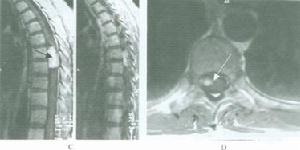

X線平片檢查約有30%~40%的患者可見骨質改變,在常規的脊柱正側位片及斜位片上,常見的徵象有:(1)椎間孔擴大或破壞;(2)椎管擴大,表現為椎弓根間距增寬;(3)椎體及附屬檔案的骨質改變,可見椎體骨質缺損、椎弓根破壞等;(4)椎管內鈣化,偶見於少數脊膜瘤,畸胎瘤及血管母細胞瘤;(5)椎旁軟組織陰影。由於椎管內腫瘤多為良性,早期X線片上常無骨質異常表現,有時僅在晚期可見椎弓根間距增寬,椎管壁皮質骨變薄椎管擴大等間接徵象。對於啞鈴形椎等內腫瘤,可見椎間孔擴大。X線片檢查,可排除脊柱畸形、腫瘤等原因造成的脊髓壓迫症,仍為一種不可缺少的常規檢查。